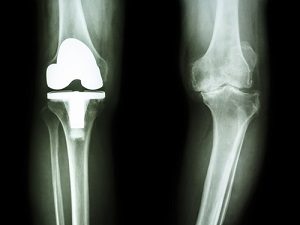

- Эндопротезирование. Замена пораженного сустава искусственным имплантом – крайняя мера, на которую идут израильские хирурги-ортопеды. При этом эндопротезирование они проводят с использованием самых передовых медицинских технологий. Импланты для каждого пациента подбираются таким образом, чтобы они максимально соответствовали анатомическим особенностям и обеспечивали полное восстановление подвижности. Отзывы о лечении суставов в Израиле свидетельствуют о том, что благодаря такому подходу врачи сводят к минимуму риски осложнений и добиваются значительного увеличения срока службы эндопротезов – от 10 лет и больше.